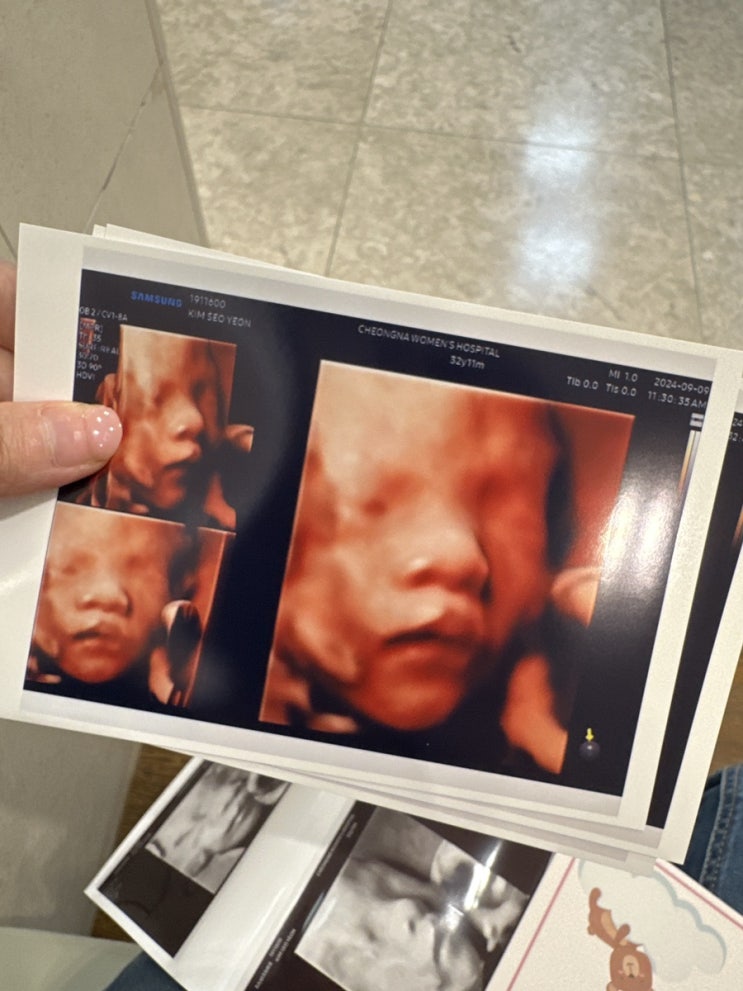

둘째 임신 - 임신 32주 청라여성병원 태동검사, 백일해 주사

하필 비가 오는....!!! 차 안가지고 걸어가려했는데 ㅠㅠ 차가지고가게됨... 역시나 주차장은 헬투더헬!!!!...